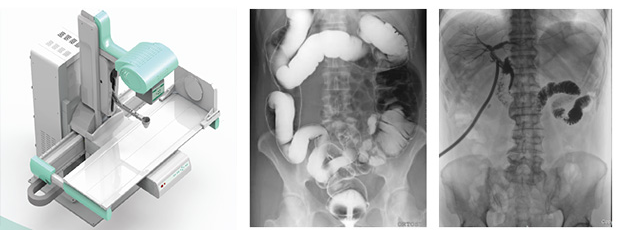

目前,普放型X射線設備領域前沿產品——動態DR已經廣泛應用于臨床影像診斷。但目前市場上也有一些類似的產品,在影像診斷上相比以前的設備都有了較大的進步,但和真正意義上的動態DR依舊有一定的差距。那么,作為消費者的我們應該怎樣才能購買到真正的動態DR?下面小編就給大家說5點,讓大家可以作為參考去進行購買,一起來了解一下吧!

1、真正的動態DR只有一個探測器

2、無需影像增強器

真正的動態DR是不用影像增強器的。雖然影像增強器在醫學影像史上有重要的歷史地位,但是隨著科學技術的日益革新,目前動態DR探測器在影像的各個領域都墊付了影像增強器的功能。

3、成像視野是17英寸方形而非7/9/12英寸圓形

目前DR的成像面積都是17英寸×17英寸方形成像,這在臨床應用中有巨大的優勢。

4、動態成像像素100萬以上,動態點片像素900萬以上

5、毫秒級動靜切換實時成像